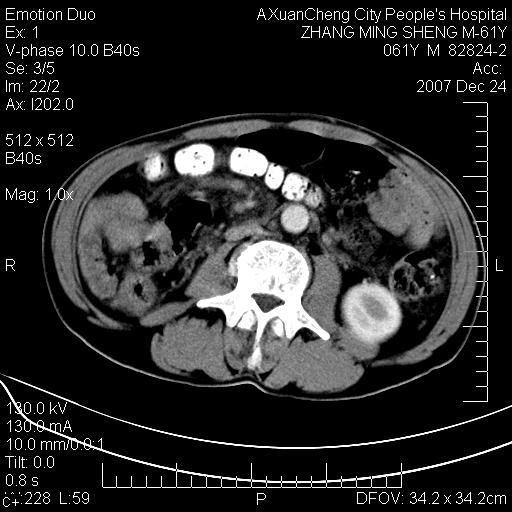

标题: CT11031:M61Y,胰腺占位

大家侃侃门静脉和胆管系统怎么回事,肝内转移?

胰腺癌肝转移

2,肝内多发结节状低密度占位,伴门脉及肠系膜上v栓子形成.考虑a;门脉及肠系膜上v血栓后肝改变.b;弥漫型肝癌伴门脉及肠系膜癌栓.

肝硬化,门脉高压,脾肿大;弥漫性肝癌,肝内、门脉、腹膜后淋巴结转移,肝内外胆管扩张,胰头区占位,建议mr检查

胰腺癌伴肝内转移;门脉、肠系膜上v癌栓形成。

考虑为:胰腺癌伴肝脏转移、腹膜后淋巴结转移,门静脉及肠系膜上静脉瘤栓形成。

胰体尾癌伴肝内转移,门静脉及肠系膜上静脉瘤栓形成.